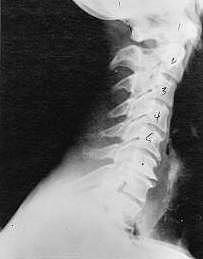

This is a side x-ray view of the neck. As with all the pictures you will see on this page, the patient is looking to the right of the screen, so you are viewing the right side of their neck. We will call this picture a "near normal" spine. Compare this spine with the ones you will see below on this page. Notice the normal forward curve of the neck. This curve helps absorb shock. Notice how each of the disc spaces between C2 (second bone in neck) and C7 are thick and even, this again is normal. Also notice how the front portions (right on the x-ray) of each of the vertebrae (called the 'body' of the vertebrae) are fairly square with clear and well defined borders. This type of arrangement is normal in the neck. Normal vertebrae in other parts of the spine also have similar characteristics to what we see here. When subluxations occur and are left uncorrected, ongoing relentless changes occur that result in damage to the structure and function of the spine along with nerve damage and the resulting problems caused from improper nerve supply.